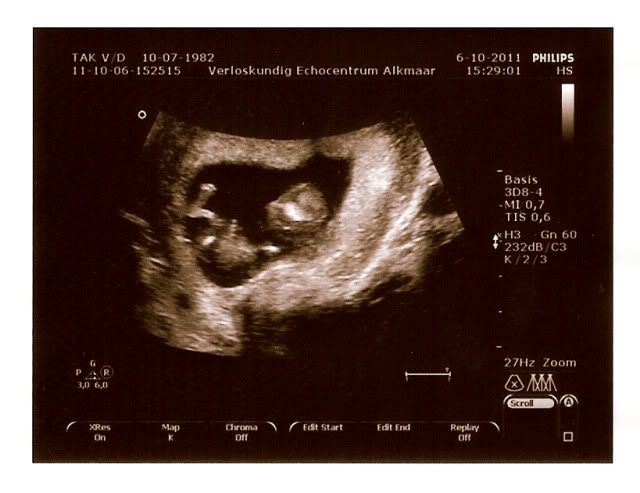

Alles is top! Buikje was goed gevuld, dus het kindje heeft een goede slik reflex, ook sloeg het hartje keurig 130/140 slagen per minuut wat we nu ook duidelijk hebben kunnen horen! En het blaasje was gevuld.

Het kleintje hoeft nu alleen nog maar te groeien, inmiddels is het 5 cm groot bijna 4,5 cm groter dan 3 weken geleden. Geweldig! We zijn helemaal blij en gelukkig!